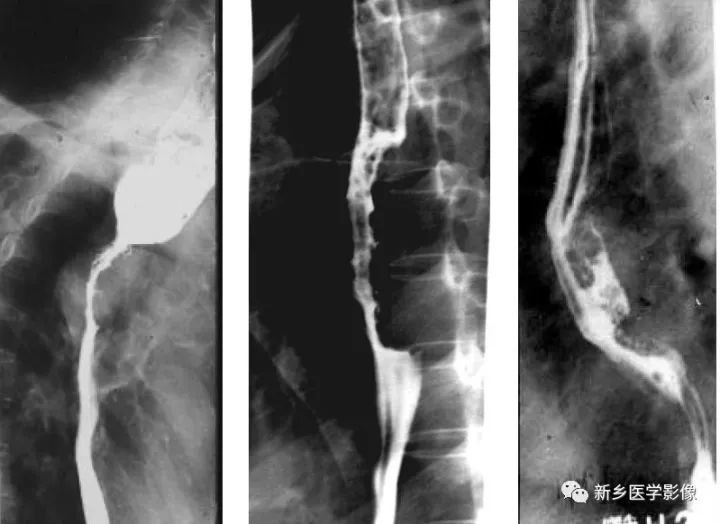

中晚期食管癌钡餐造影图像

a、浸润型食管癌,显示食管上段向心性狭窄,边缘不规则,局部见软组织肿块,狭窄以上食管扩张

b、增生型食管癌,食管中段偏心性不规则充盈缺损,边缘不规则

c、溃疡性食管癌,食管中段偏心性肿块,局部见腔内龛影